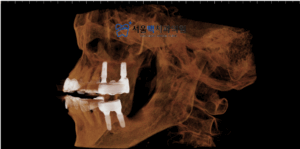

위 어금니의 자리의 임플란트 식립은

‘상악동’이라는 빈 공간이 뚫리지 않게

식립하는 것이 매우 중요하고 어려운데요.

가양역치과, 서울맥치과는

철저한 해부학적 분석과 실력으로

안정적으로 임플란트 식립을 마무리해드리고,

CT를 통해 3차원 사진으로 환자분께 수술 후 상태를 설명드렸습니다.